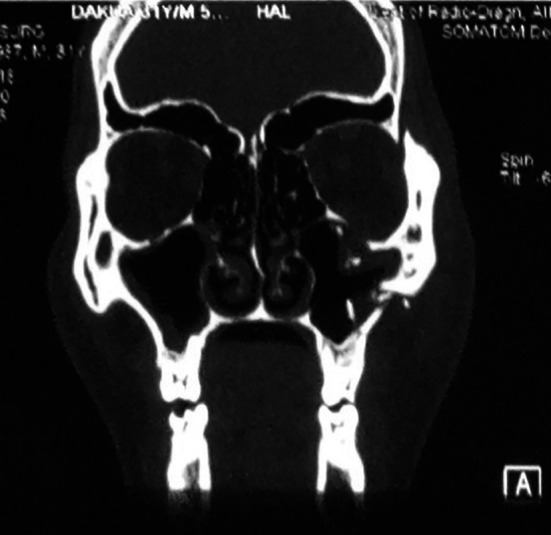

Fracture lines those were severely comminuted (Figs. 2, 3 and 4), sagittal fractures (Fig. 5), involving orbital complex, orbital floor fractures (n = 20) (Fig. 6), fractures associated with globe injuries and fracture lines characteristically involving the body of zygoma but not the processes were included in atypical group (Fig. 5).

Fig. 6.

Orbital fractures